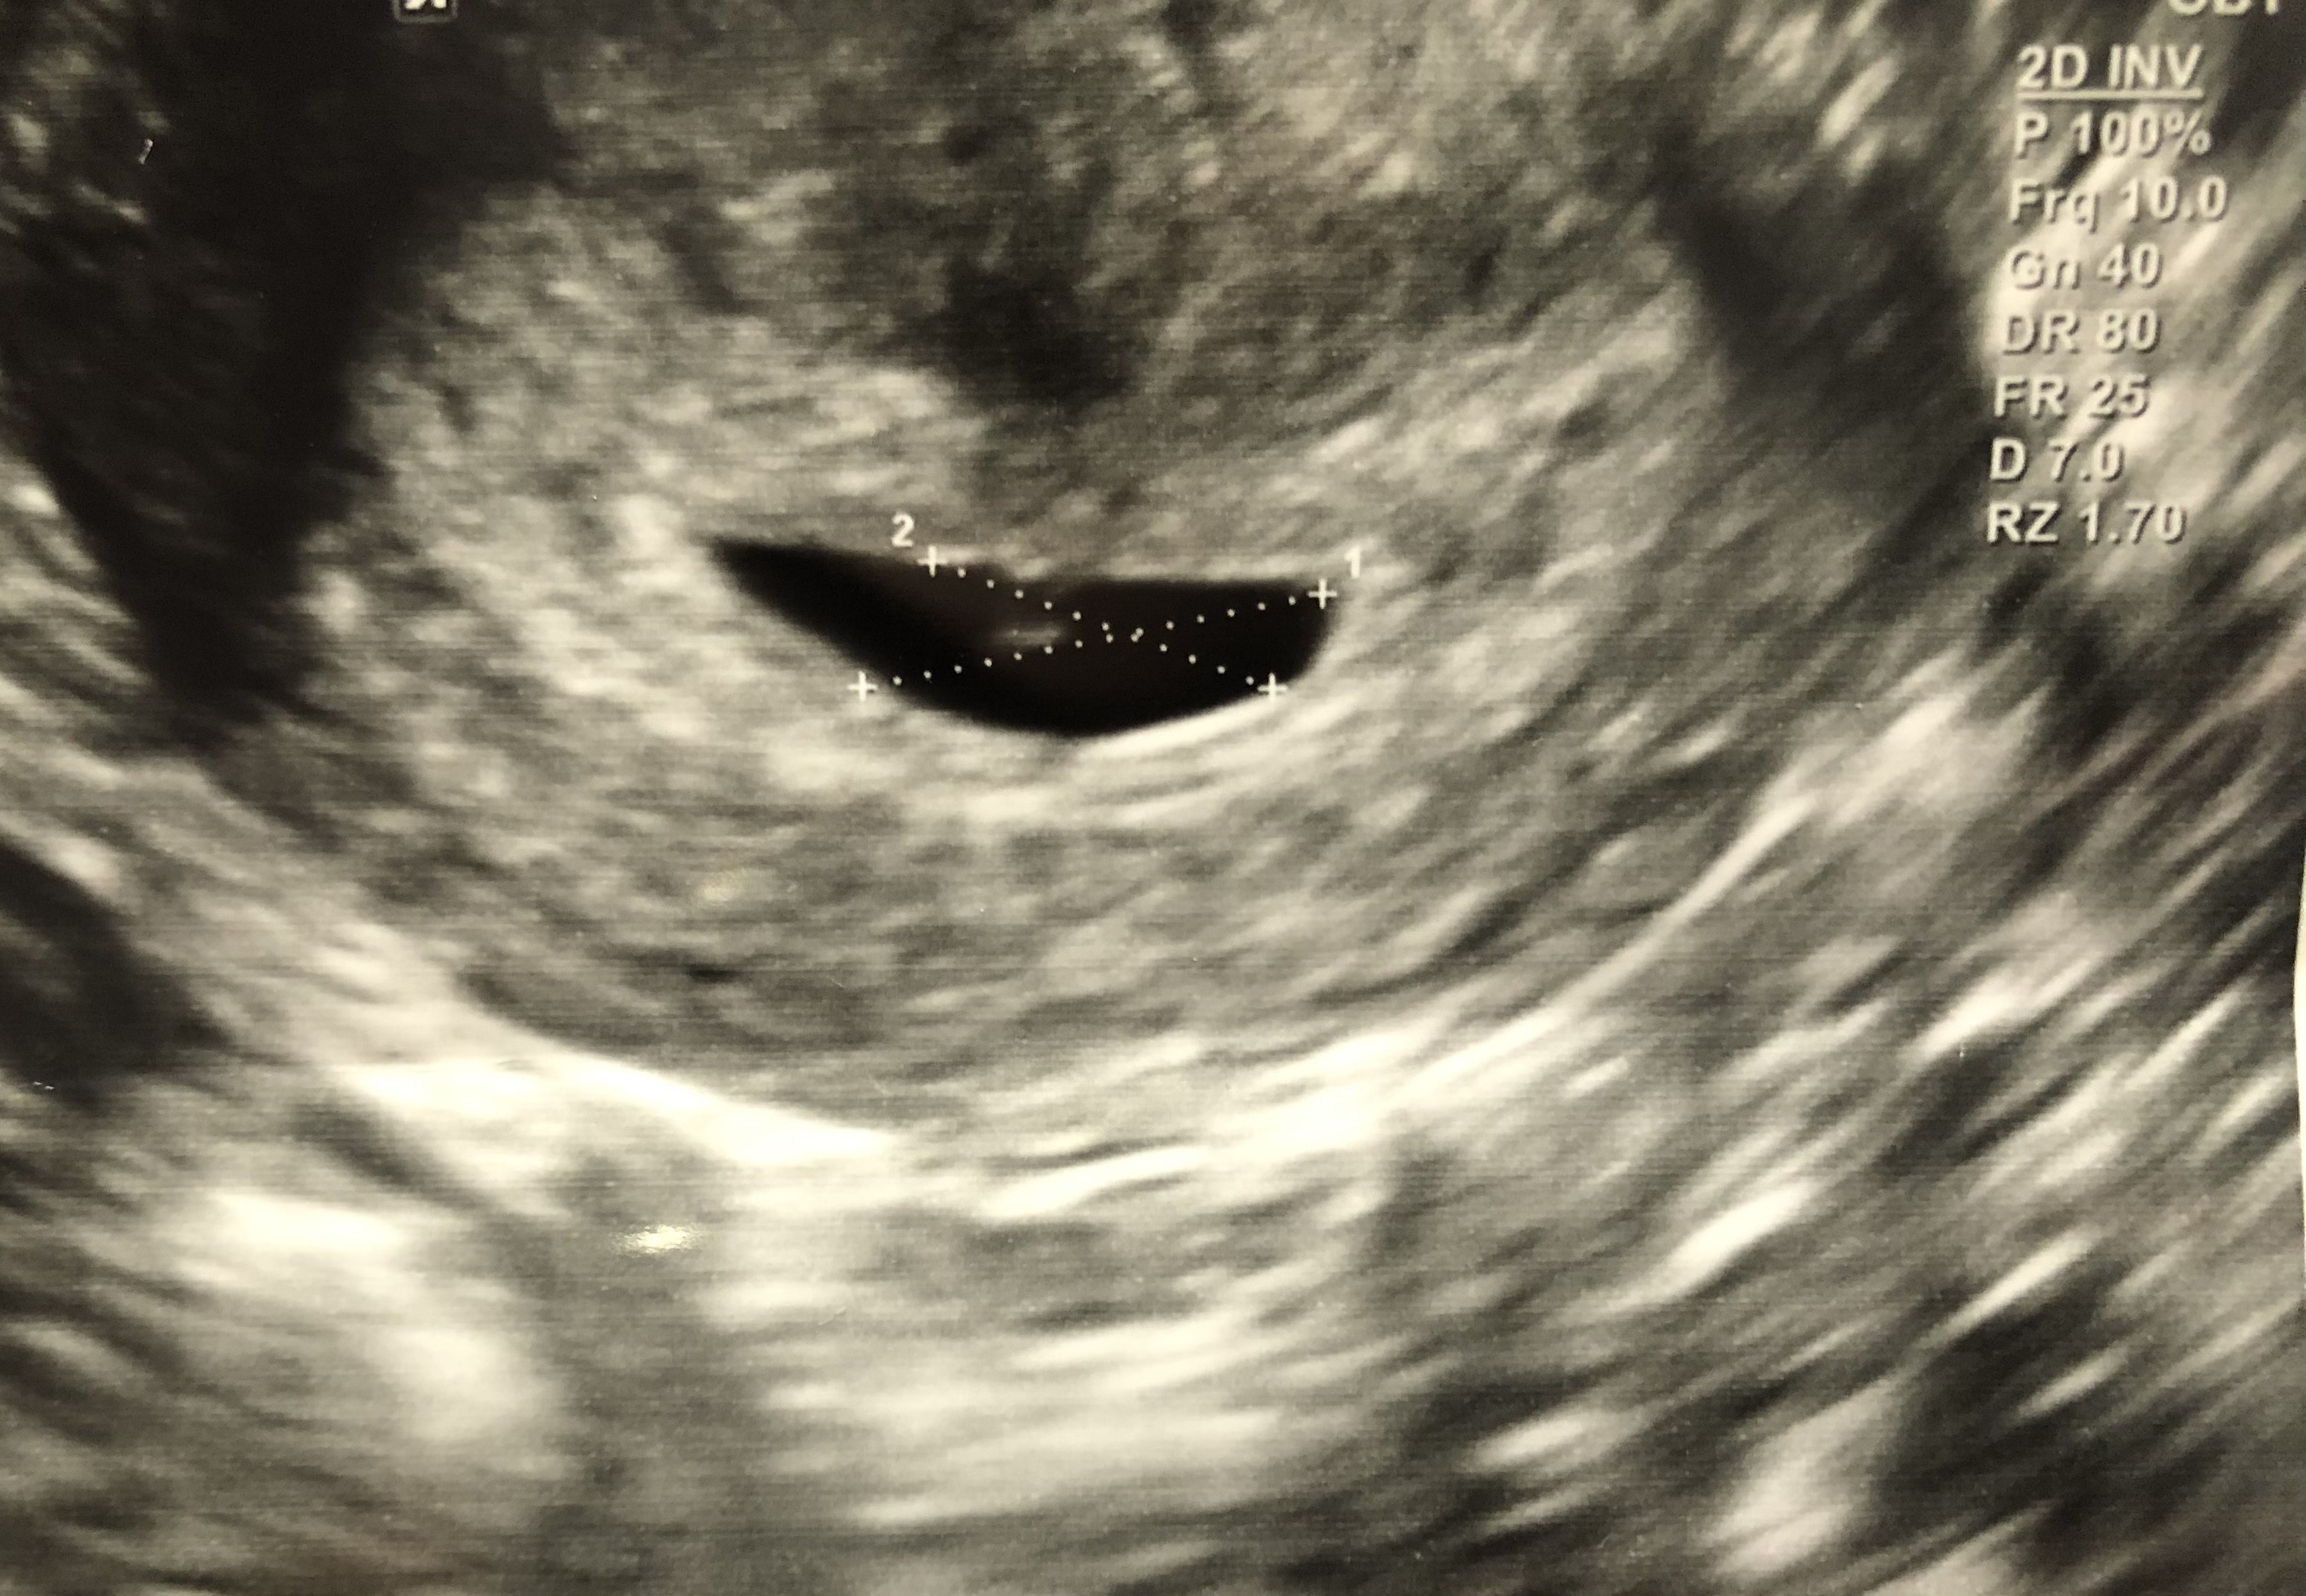

Dziewczyny a która ma ostatnia pierwszą wizytę. Czy wszystkie mają już jasną sytuację? Pytam pod kątem ewentualnego wątku prywatnego.